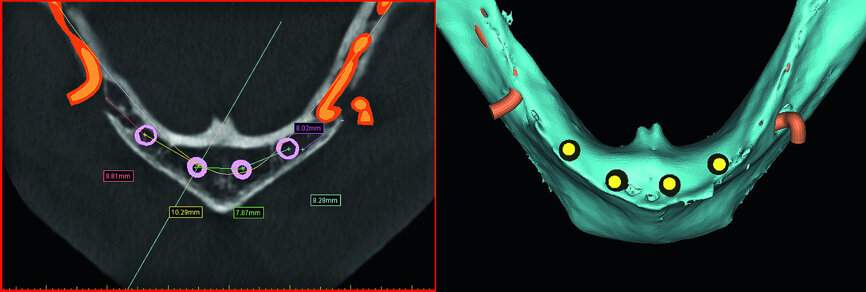

The CBCT data provides us with much more information and clinicians should consider ALL of the views afforded by the CBCT scan data and use the tools of the planning software to simulate the positioning of the implants, such as the axial and cross-sectional views. The right and left inferior alveolar nerves (IAN) were traced to determine the available width in the anterior symphysis for implant placement. It was determined that four standard diameter implants could be positioned to support an overdenture as desired by the patient (Fig. 9).

The cross-sectional images revealed the presence of a thick facial buccal plate of bone in some areas, thinner in others, and a thick lingual plate of bone generally. The surprise was in the symphysis, a hollow area in the anterior central area exactly where implants would be placed! Other hollow areas and intraosseous vessels were noted (see arrows, Fig. 10). The ‘hollow’ areas in the anterior symphysis are as illustrated in the 3-D reconstructed volumes with four simulated implants in an occlusal view.

The hollows in the anterior symphysis area of the mandible are seen in a ‘clipping’ view with simulated implants, slicing through the 3-D volumetric reconstruction (Figs. 11a & b). This anatomical variation could not be determined with 2-D imaging modalities. Once this was known, the planning of implants could proceed with the knowledge of the individual patient’s anatomical presentation. The patient was informed of the issues related to the anatomy as shown on the 3-D simulation from the CBCT scan. These images are invaluable to educate the patient and improve case acceptance, and extremely invaluable for the diagnostic process in determining the best surgical approach. Proper diagnosis and treatment planning through 3-D imaging and simulation software revealed that the narrow ridge would have been a significant obstacle using a flapless approach, and the hollows in the bone may have caused significant issues in the placement and the ability to stabilise the four implants that were eventually placed.